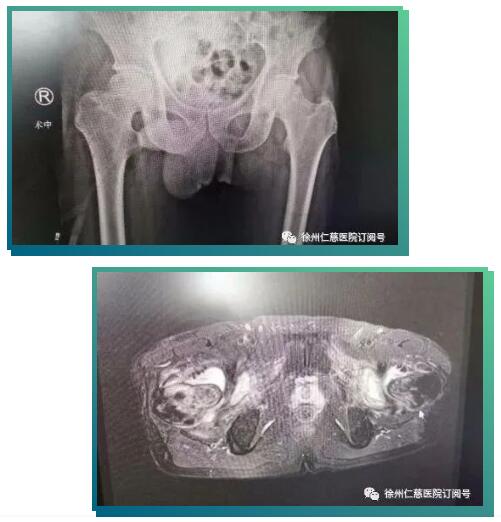

接诊的关节科邱东新副主任医师询问病史,给李师傅做了仔细的检查,磁共振片显示患者双侧股骨头坏死,同时患有腰椎间盘突出、椎管狭窄、腰椎不稳(这是引起腰痛的原因)。患者的双髋疼痛在当地以为是腰痛引发,来必威官方首页官网betway后,邱医师经过仔细检查,发现髋部疼痛其实是由股骨头坏死引起的;目前患者的股骨头坏死尚处于早期阶段,还能采取保髋治疗;如果直接置换关节,不仅创伤大,且因患者年纪不大,还要考虑未来假体翻修的问题,综合考虑之后,邱医生决定采用骨科机器人辅助完成保髋手术。

完善的术前准备后,6月17日,邱东新、徐猛、杨沛霖手术团队给患者进行了机器人辅助下双侧股骨头坏死髓芯减压术,骨科机器人在主刀医生的操纵下精准地“定位聚焦”病灶,设计好进针点,通过骨科机器人机械臂的引导,将导针分毫不差地均匀打入股骨头坏死病灶,达到病灶彻底减压的目的。手术全过程无切口,仅有三个极小的钉道口。

传统股骨头髓芯减压植骨术,需要在X线下定位至坏死区,即便是有经验的医生也需要多次透视和尝试才能打入导针,这一过程增加了患者的创伤和手术时间,且不能准确彻底去除坏死病灶。

而骨科手术机器人系统只需在采集图像后,设计导针方向和位置,按设计一步到位精准地将导针置入规划位置,将坏死区各角度彻底减压,达到缓解症状,减轻疼痛,延缓股骨头坏死进展的目的,并尽可能推延或避免髋关节置换手术,真正体现了“精准微创”的治疗理念。